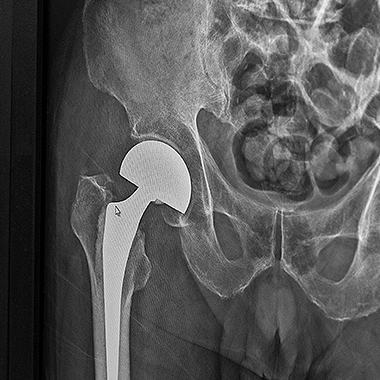

Jest to jeden z najbardziej zaawansowanych i precyzyjnych sposobów operacyjnego leczenia biodra, który pozwala na przeprowadzenie zabiegu bez przecinania mięśni, przez naturalne przestrzenie anatomiczne. Technika ta zyskuje coraz większe uznanie w leczeniu choroby zwyrodnieniowej stawu biodro wego, szczególnie wśród pacjentów poszukujących szybszego powrotu do aktywności.

Zabieg wykonuję z użyciem wysokiej jakości, nowoczesnych implantów dobieranych indywidualnie do budowy anatomicznej i potrzeb pacjenta. Całość leczenia opiera się na zasadach tzw. szybkiej ścieżki (fast-track), co oznacza także odpowiednio zaplanowaną rehabilitację i stały nadzór pooperacyjny. Dzięki takiemu podejściu, endoprotezoplastyka biodra w moim wykonaniu stanowi skuteczną i bezpieczną metodę leczenia zwyrodnienia stawu biodrowego – szczególnie dla pacjentów oczekujących szybkiego powrotu do sprawności.